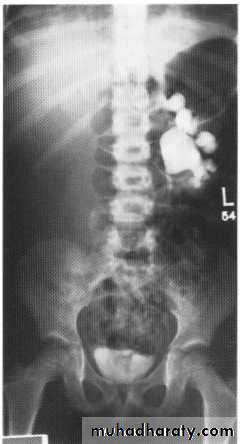

Polycystic kidneys

I n autosomal recessive polycystic disease of the kidneys (ARPCK) the renal parenchyma is replaced by numerous tiny (1-8 mm) cystsOn IVU there is a striated nephrogram thought to be due to contrast lying in the minority of preserved functioning tubules next to dilated non-opacified diseased tubules.

Polycytic disease

In autosomal dominant polycystic disease of the kidneys(ADPCK) numerous cysts of varying size, often becomingextremely large, develop within the kidneys, gradually replacingnormal renal parenchyma and ultimately producing renal failure. It usually presents between 20 and 39 years of age